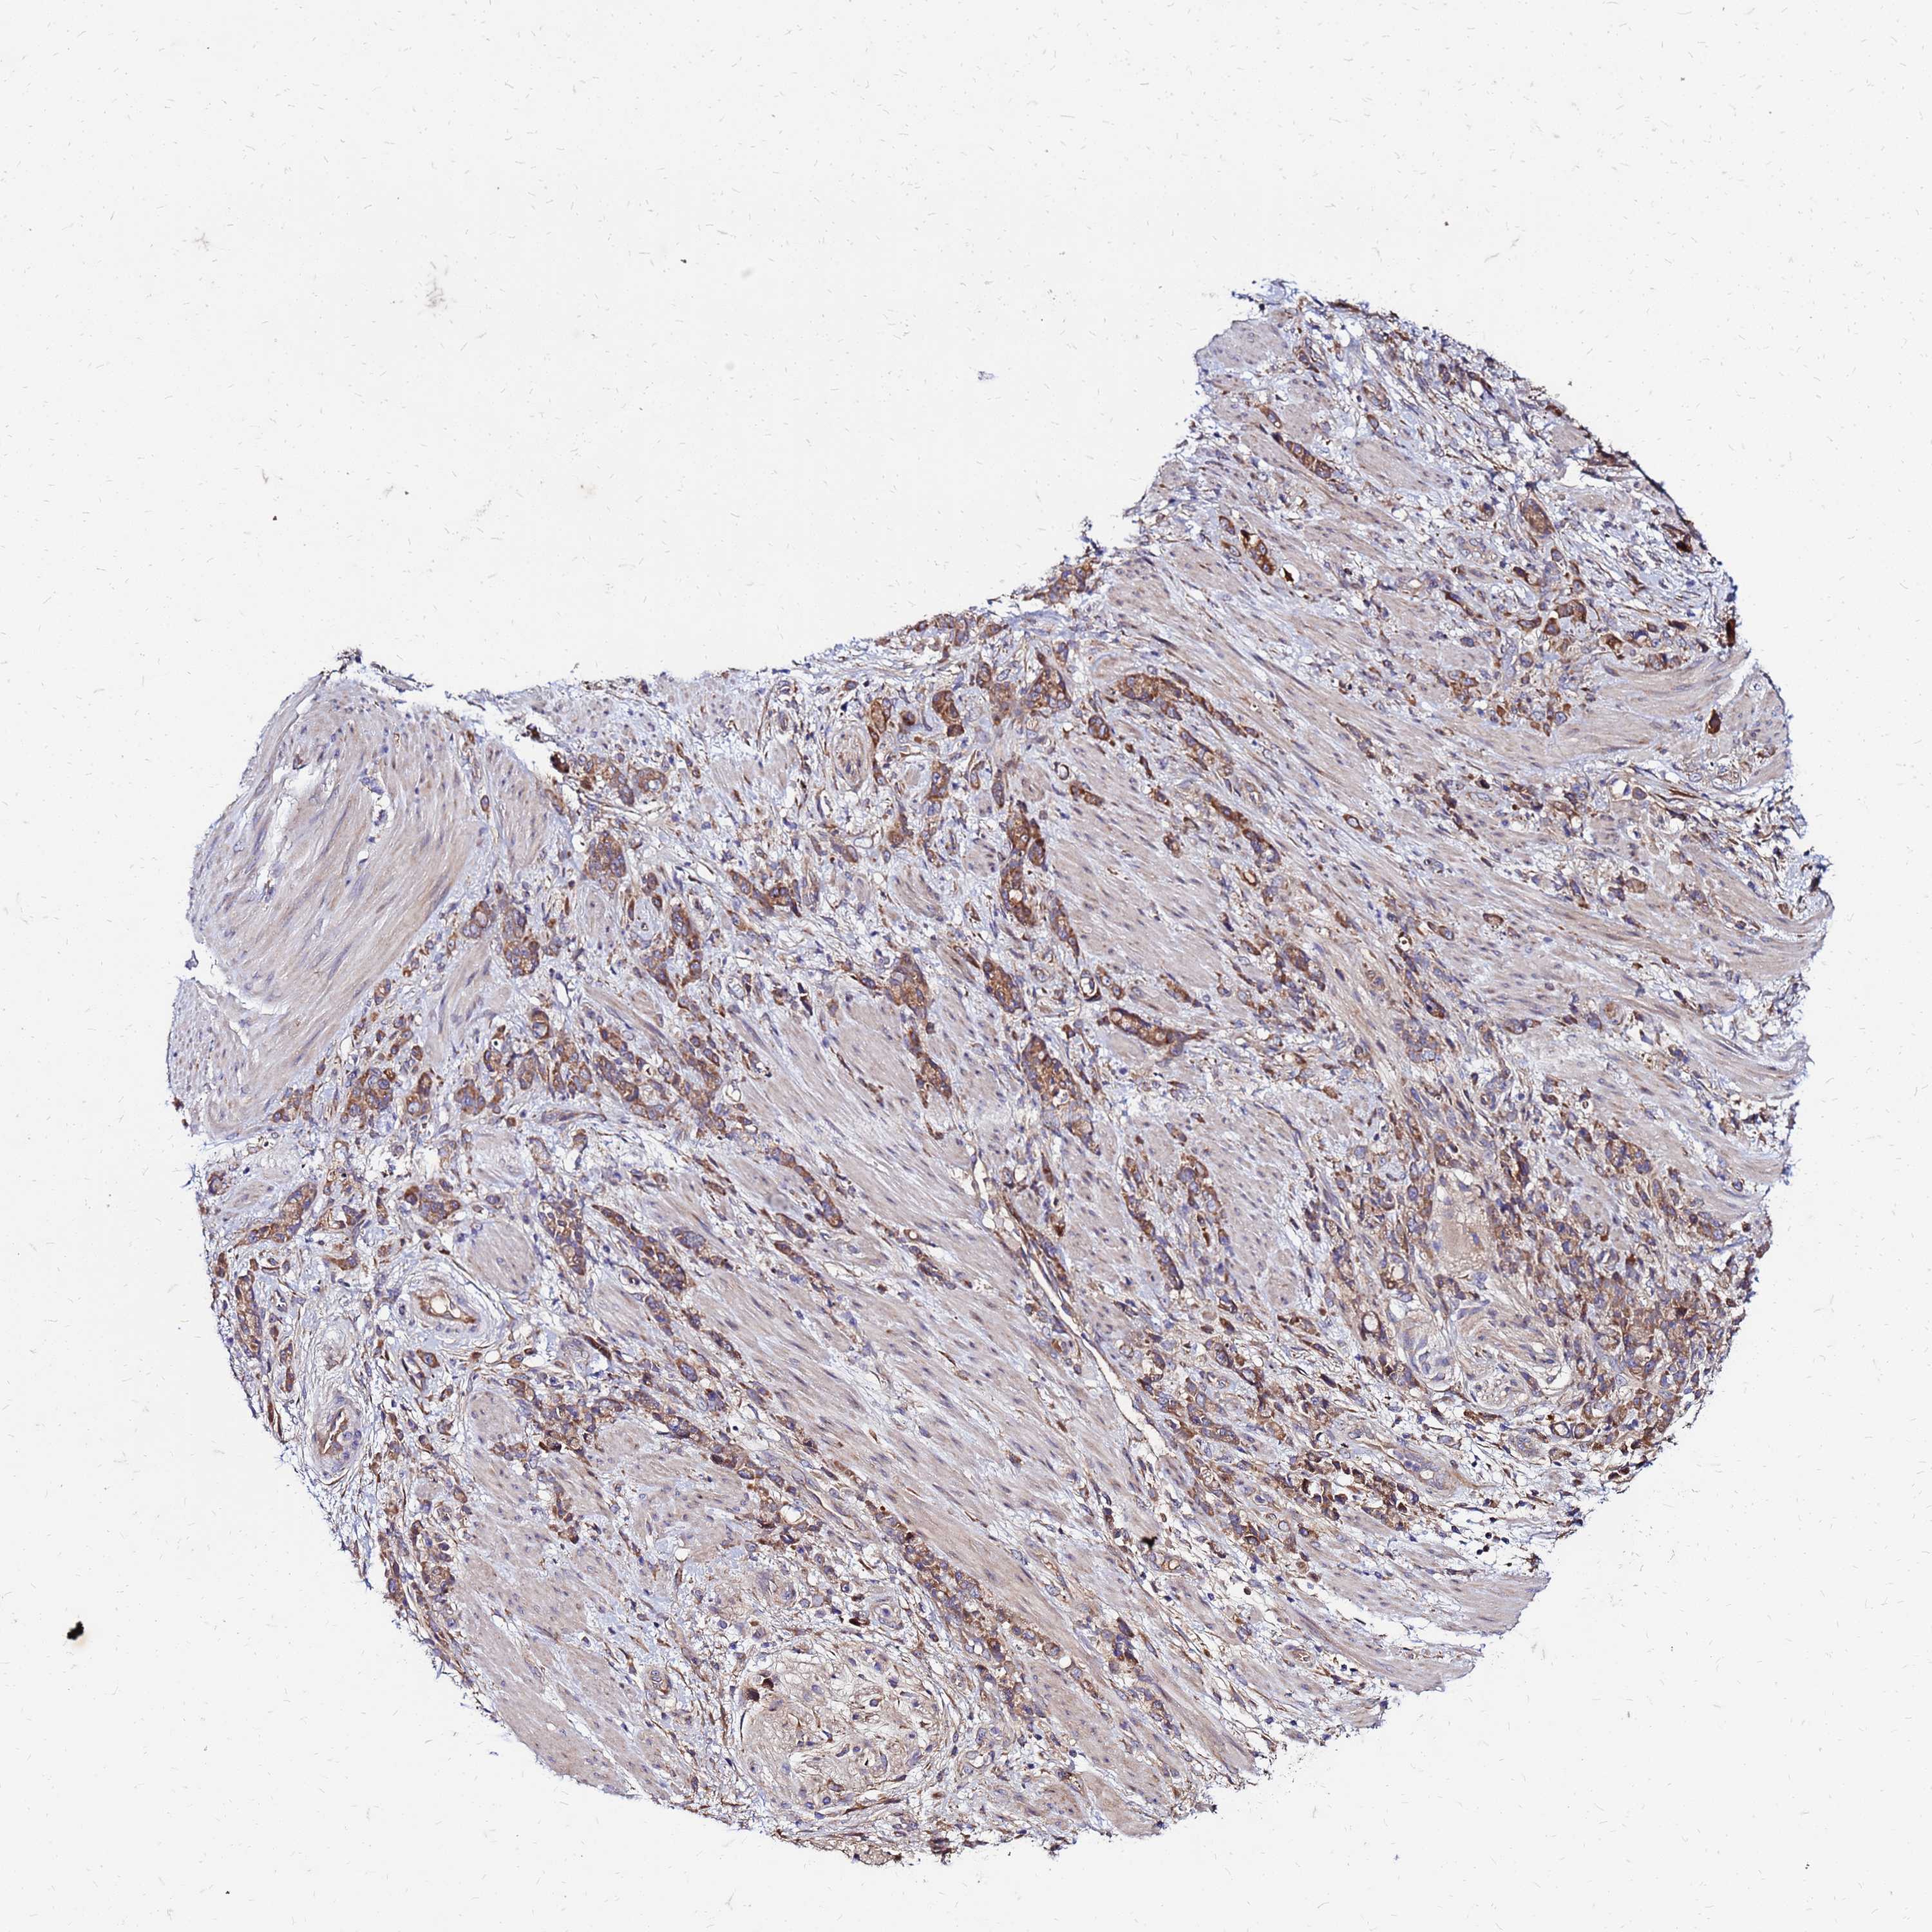

STOMACH CANCER - Protein expressioni

A mouse-over function shows sample information and annotation data. Click on an image to view it in a full screen mode. Samples can be filtered based on level of antibody staining by selecting one or several of the following categories: high, medium, low and not detected. The assay and annotation is described here.

Note that samples used for immunohistochemistry by the Human Protein Atlas do not correspond to samples in the TCGA dataset.

Antibody stainingi

Antibody staining in the annotated cell types in the current human tissue is reported as not detected, low, medium, or high, based on conventional immunohistochemistry profiling in selected tissues. This score is based on the combination of the staining intensity and fraction of stained cells.

Each image is clickable and will lead to virtual microscopy that enables deeper exploration of all samples and also displays staining intensity scores, fraction scores and subcellular localization as well as patient and tissue information for each sample.

Antibody HPA023038

Staining

High

Medium

Low

Not detected

Intensity

Strong

Moderate

Weak

Negative

Quantity

>75%

75%-25%

<25%

None

Location

Nuclear

Cytoplasmic/membranous

Cytoplasmic/membranous,nuclear

Adenocarcinoma, NOS